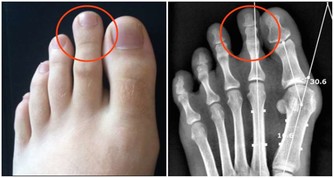

此外,痛風、肥胖等也會引起慢性腎衰,同樣要注意。